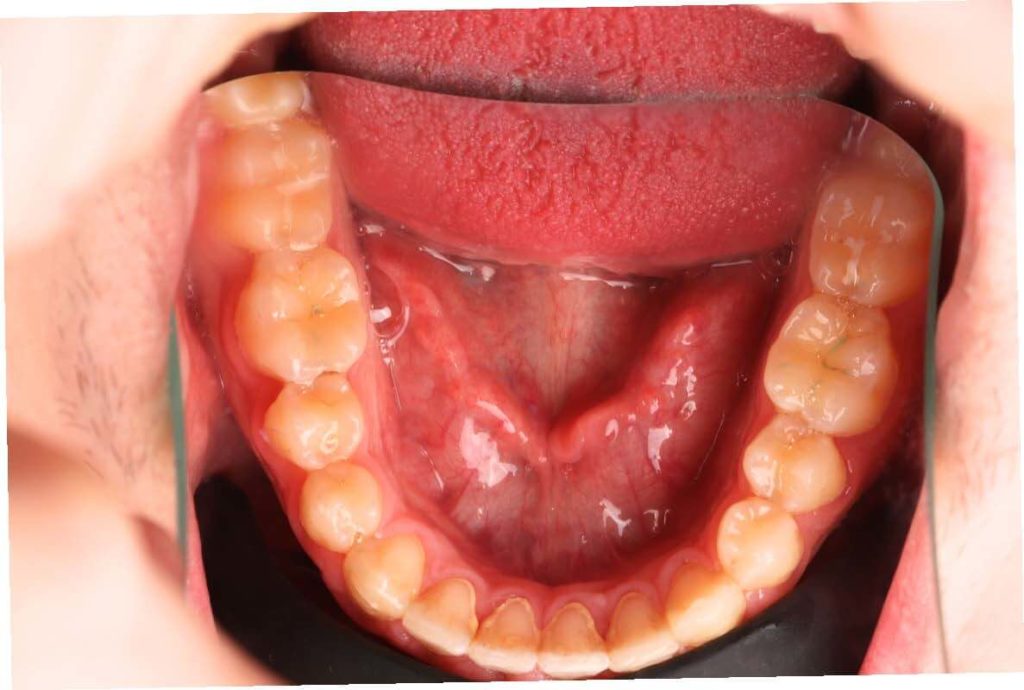

SITUACIÓN INICIAL

CLASE I MORDIDA CRUZADA EN LATERALES

• Apiñamiento moderado en el arco superior e inferior.

• Arco normal con necesidad de expansión.